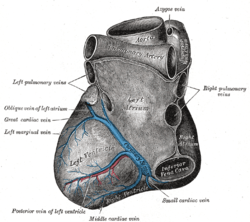

The position and relation of the esophagus in the cervical region and in the posterior mediastinum. Seen from behind. Left atrium

Left atrium